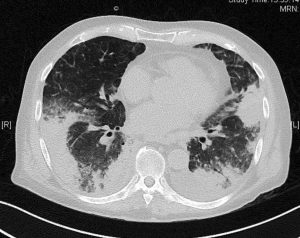

Pneumonie hypoxémiante : ne pas la banaliser !

Monsieur S Alexandre est âgé de 87 ans. En juillet 2015, un purpura thrombopénique idiopathique (PTI) lui a été diagnostiqué. Le patient était à l’époque en très bon état général,…